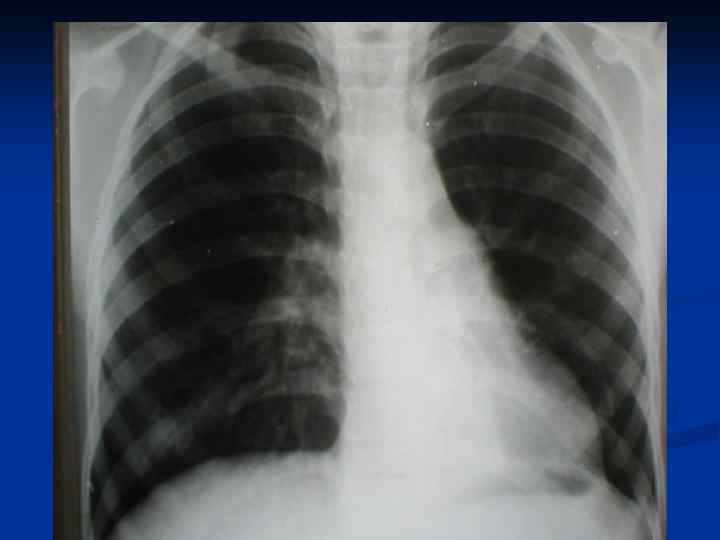

Рентгенология n Вздутие пораженных отделов легкого с медиастинальной грыжей, органы средостения смещены в здоровую сторону. n Бронхография выявляет (суб и компенсированные формы) – сужение и деформация долевого бронха и обрыв мелких бронхов со смещением ветвей сдавленных отделов легкого. Бронхи коллабированных долей легкого сближены и собраны в «метелку»

Лобарная эмфизема